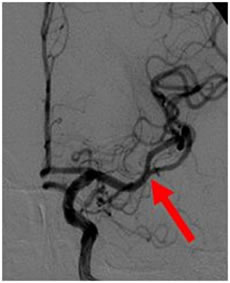

2例目を紹介いたします。81歳女性、自宅にて意識がなく、倒れているところを発見されました。来院時、JCS200と重篤な意識障害、左共同偏視、右片麻痺を認めました。頭部MRIにて脳幹に淡い梗塞、(図1)MRAにて脳底動脈の閉塞を認めました。(図2)再開通しなければ、死亡率が高い病態です。緊急にて血管撮影を行い、脳底動脈の閉塞を認めました。(図3)Penumbra吸引カテーテルと血栓除去用ステント(Trevo provue 4×20mm)を用いて血栓除去を行い、TICI3の完全再開通を認めました。(図4)翌日のMRIでは脳幹に梗塞を認めるも、(図5)意識障害は急速に改善しました。超高齢なために、約2ヶ月間のリハビリテーションを経て自宅へ戻りました。

図4:Penumbra血栓吸引カテーテルと血栓除去用ステントを用いて血栓除去を行い、TICI3の完全再開通を認めました。 |